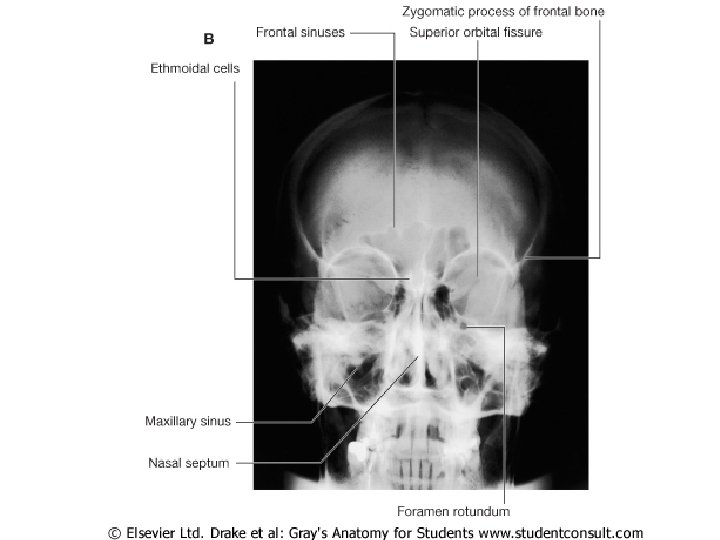

Paranasal Sinuses

Maxillary sinus

Frontal sinus

Ethmoidal sinusitis

Nasal meatus • Sphenoethmoidal recess: sphenoidal sinus • Sup. Meatus: post. Ethmoidal sinuses •

Nasal meatus • Sphenoethmoidal recess: sphenoidal sinus • Sup. Meatus: post. Ethmoidal sinuses • Middle meatus: -Bulla ethmoidalis← middle ethmoidal air sinuses Hiatus semilunaris← maxillary sinus, infundibulum Frontal sinus, ant. Ethmoidal air sinuses • Inf. Meatus ← nasolacrimal canal